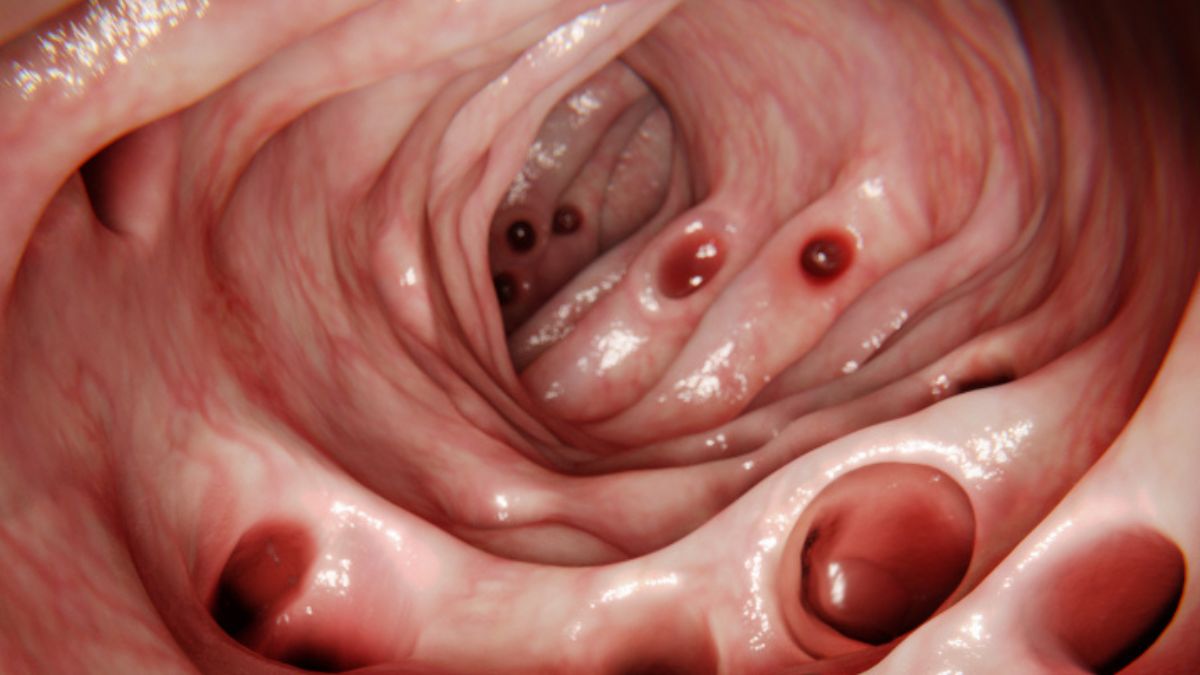

By the time most people reach the ripe age of 80, the smooth lining of their digestive tract is scattered with small, bulging pouches of tissue.

These sac-like protrusions along the digestive tract, called diverticula, are ‘weak spots‘ in the gut’s muscular wall. They are typically harmless, and most people never even know they are there.

Sometimes, after a colonoscopy, patients are alarmed to find they have developed diverticulosis, but most of the time, this condition is nothing to worry about.

While diverticula can develop in the large and small intestine, around 95 percent of patients in the Western world have diverticula in their sigmoid colon.

This part of the digestive tract works under great pressure to push feces into the rectum.

Diverticulosis can typically be diagnosed with a CT scan or colonoscopy.